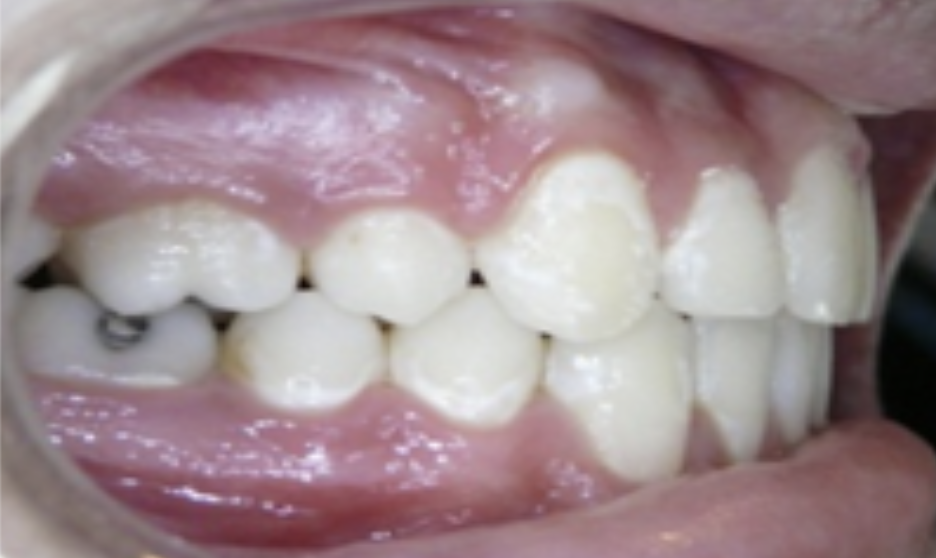

Protrusion

Upper teeth stick out beyond the lower teeth.